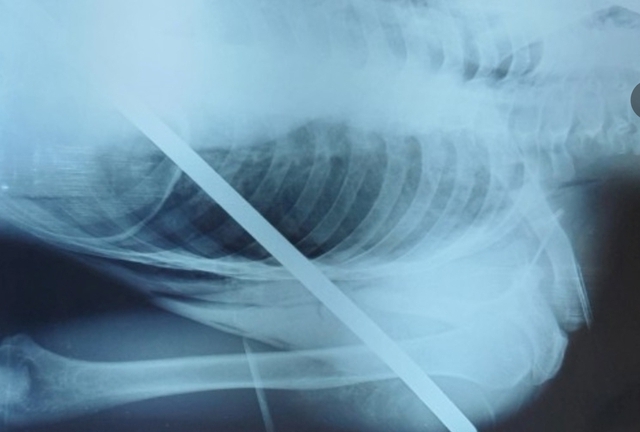

Các bác sĩ nhận định, cây đinh dài khoảng 3cm găm qua xương sọ của bé, có nguy cơ gây rách màng cứng, gây tổn thương não, cần phải phẫu thuật để xử lý sớm.

Lúc này, các bác sĩ đã tiến hành thực hiện các kỹ thuật để rút cây đinh ra khỏi đầu bé, rửa vết thương, cầm máu, đóng vết mổ. Chỉ trong 45 phút các bác sĩ đã thực hiện thành công ca phẫu thuật.